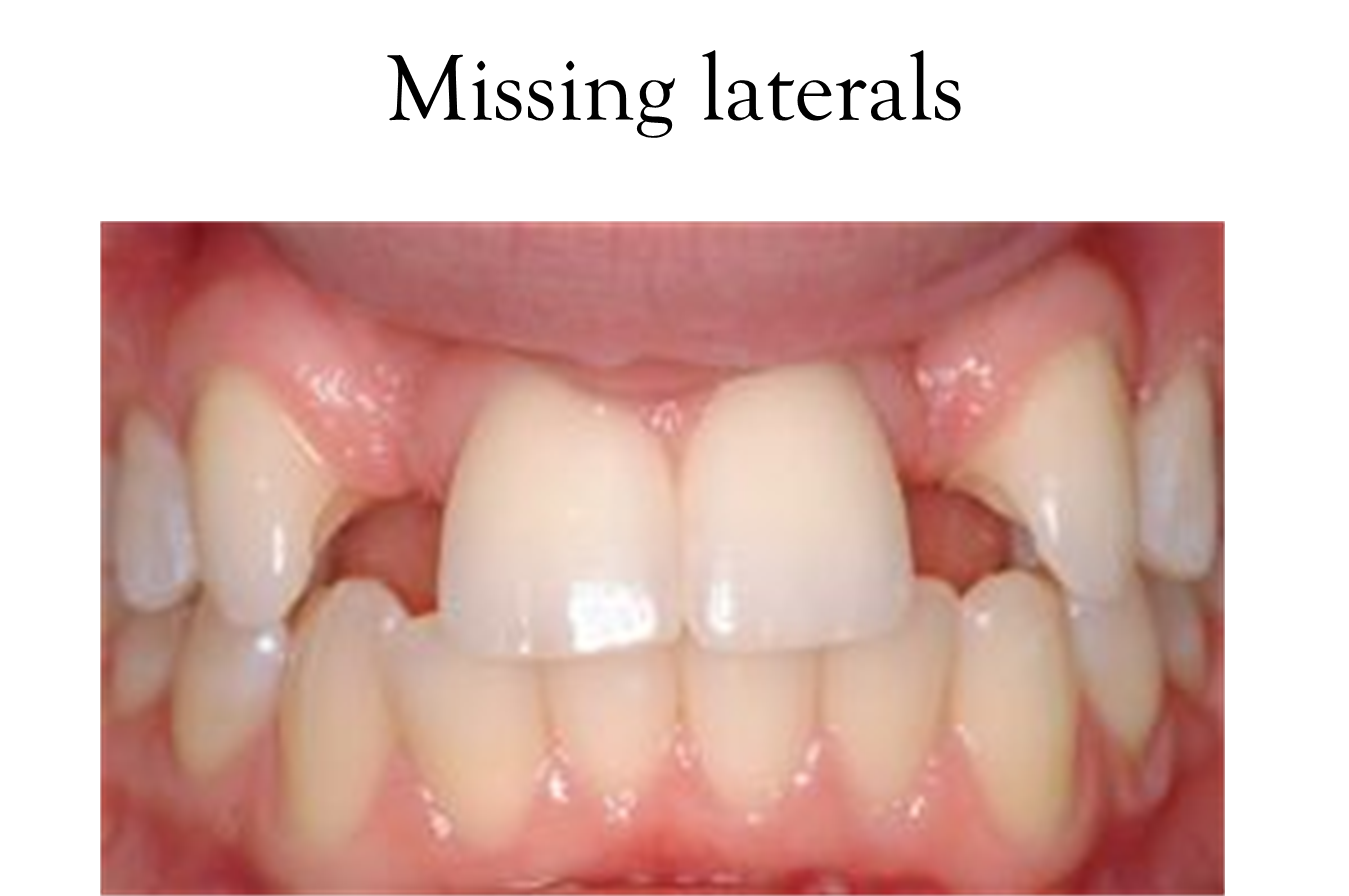

Incisors: Located in the anterior segment, with 2 in each quadrant

Canines: Positioned immediately posterior to the incisors, 1 in each quadrant